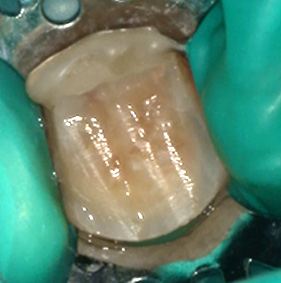

6日目(術後3-4週目) 歯内治療を開始します。

術後4週目の移植した歯牙。固定は維持されている。

ラバーダム(ゴム製の布)を装着し、歯の中の治療をします。 -